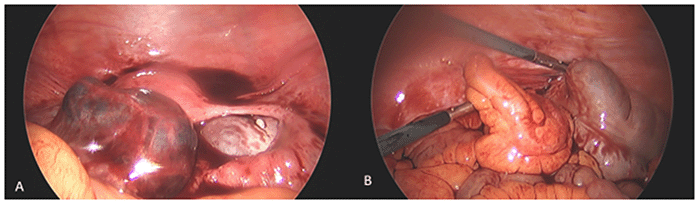

Following consultation with general surgery, a joint laparoscopic exploration was performed by the obstetrics/gynecologist and general surgeon. Access was achieved via an infraumbilical port with additional suprapubic and left lower quadrant trocar placements. Intraoperative findings (Figure 2) included a dilated left fallopian tube with approximately 200 mL of blood clots and blood products in the pelvis as well as a thickened and dilated appendix and mesentery.

Figure 2. Intraoperative Findings. Published with Permission

(A) Dilated left fallopian tube containing approximately 200 mL of blood clots. Blood products are also visualized within the pelvis; (B) Thickened and dilated appendix with a thickened mesentery